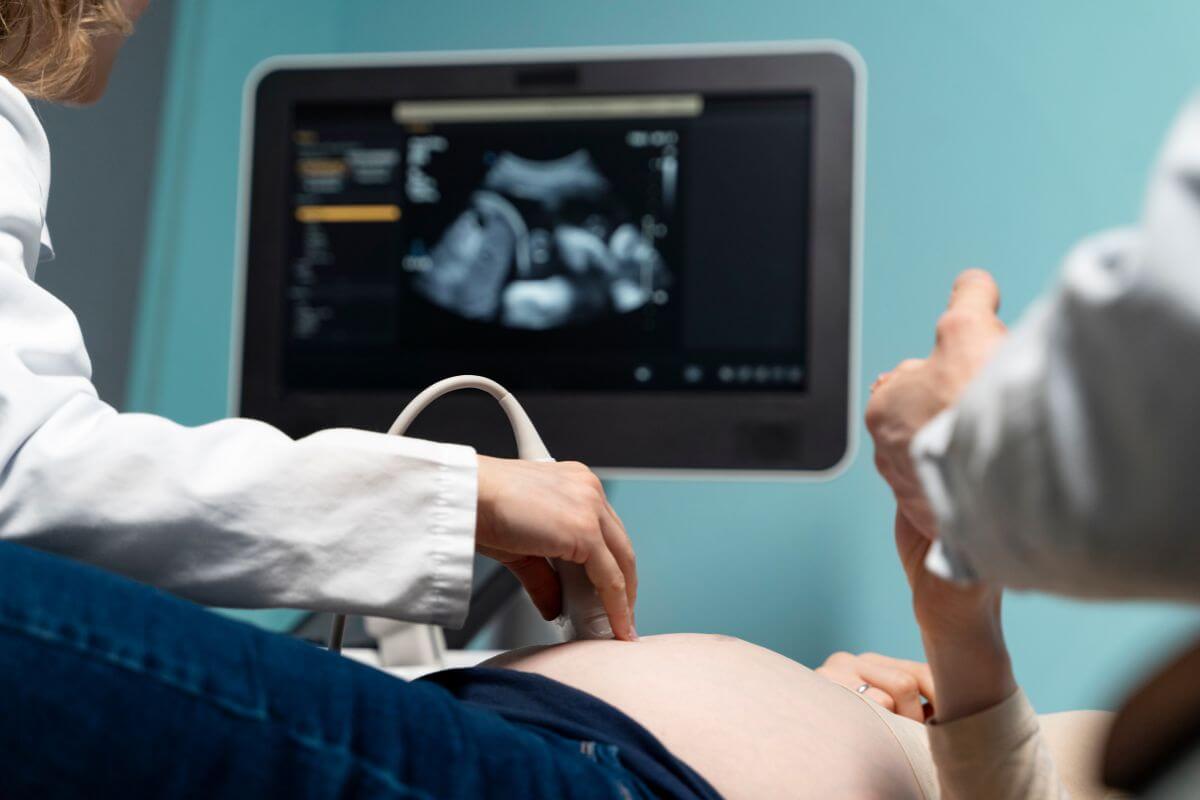

Ultrahang terhesség alatt – Van-e kockázata a magzatra nézve?

A terhességi ultrahangvizsgálatok teljesen biztonságosak mind az anya, mind a magzat számára, mivel nem járnak ionizáló sugárzással és nem okoznak sejtkárosodást. A várandósság alatt alkalmazott ultrahang célja a magzat fejlődésének ellenőrzése, az esetleges rendellenességek kiszűrése, valamint a terhesség korának pontos meghatározása.

A terhesség során leggyakrabban 2D ultrahangot használnak, amely síkbeli képet ad a magzatról. Az első trimeszterben a vizsgálat hüvelyi úton is történhet a jobb képminőség érdekében, míg a későbbi időszakban a hasfalon keresztül végzik. A 3D és 4D ultrahang részletgazdagabb képeket biztosít, amelyek nemcsak diagnosztikai, hanem esztétikai célokat is szolgálhatnak, de az ezek során alkalmazott hanghullámok nem erősebbek, mint a hagyományos ultrahang esetében, így nem jelentenek nagyobb kockázatot. A megfelelő gyakorlatok betartásával az ultrahang a legkíméletesebb és legmegbízhatóbb módszer a magzat állapotának nyomon követésére.